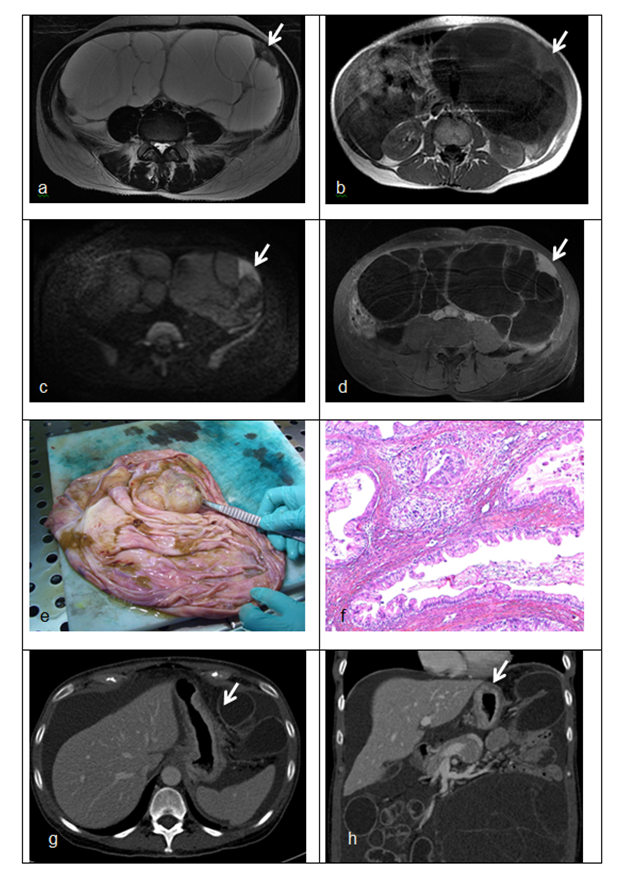

病理学表现

胃癌卵巢转移患者卵巢病灶主要表现为多形性印戒细胞和明显增生的间质细胞密切混合,形成多个界限不清的结节,肿瘤以印戒细胞为主,同时可见腺体、小管、小梁、细胞巢结构。

直肠癌卵巢转移患者肿瘤主要为中等大小的腺体,单个或形成筛状结构,上皮复层,异型性和去黏液性明显,部分区域类似于卵巢子宫内膜样癌的结构。

阑尾肿瘤卵巢转移患者,阑尾主要为低级别黏液性肿瘤,卵巢病灶表现相似,均为丰富的、分割性、细胞外黏液和黏液性增生上皮,黏液上皮表现为杂乱、不规则分布及不完整的腺体,黏液上皮异型性小,单层或局灶复层。

1A:胃癌卵巢转移,可见弥漫分布的多形性印戒细胞和致密的梭形细胞间质 HE × 200;1B:结肠癌卵巢转移,可见肿瘤细胞排列成腺样或筛状结构 HE × 40;1C:结肠癌卵巢转移,可见 ” 污秽性坏死 ” 和 ” 节段性坏死 “ HE × 100;1D:阑尾低级别黏液性肿瘤卵巢转移,可见丰富的、分割性、细胞外黏液和黏液性上皮,上皮细胞轻度异型 HE × 40